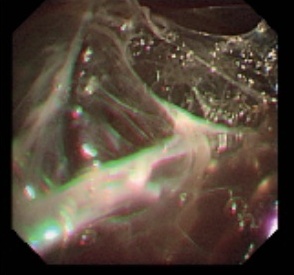

病史摘要:70 岁男性患者,因“反复肤黄尿黄 10 年余,咳嗽、胸闷 3 天”入院。既往有高血压、糖尿病史,2015 年服中成药后出现肤黄尿黄、肝功能异常,2024 年外院 MR 提示肝硬化,2025 年 4 月症状加重,多种指标异常,加用 UDCA 治疗;5 月我院诊断自身免疫性肝炎,予甲泼尼龙及吗替麦考酚酯治疗。此次入院前 3 天出现全身无力、头晕、咳嗽、胸闷。 诊疗过程:入院查体生命